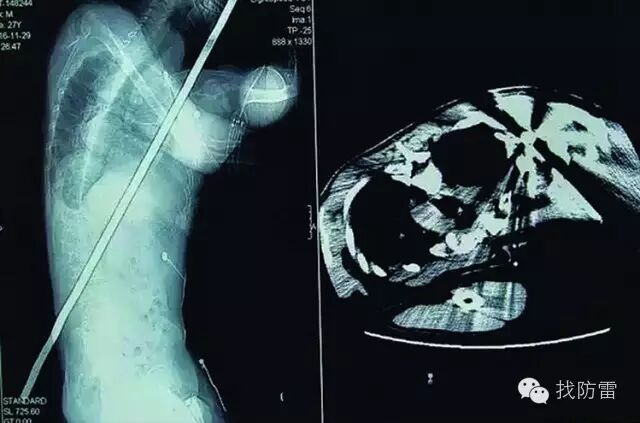

“钢管从右肩贯穿胸腔、肺叶、膈肌、肝脏右叶、肠、右肾等几个器官,处理要极为谨慎。”该院副院长孙春汉介绍,该院快速召集消防官兵、麻醉科、肝胆外科、心胸外科、泌尿外科、输血科等相关负责人讨论救治方案,为可能出现的情况制定出几套周密的预想与解决措施,统一意见后进行紧急施救。

患者麻醉后,心胸外科首先进行手术探查,医生赶紧为患者修补肺叶,紧接着探查了腹腔,发现钢管已贯穿右肝叶及右肾上极,从后侧右腰背穿出,医生在直视下小心翼翼地拔除异物,并对肝肾等进行了修复。术中出血量达1500ml,用时近3小时。

“避雷针长约2米,直径约2厘米,因为未伤及心脏及大血管,且避雷针外缘光滑,所以未导致大出血。加上手术及时,患者算很幸运。”孙春汉说。术后患者被送入ICU,现已转入普通病房进行观察治疗,情况稳定。